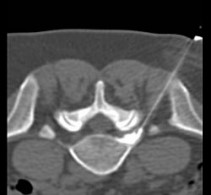

Under computer tomographic or magnetic resonance imaging control, drugs are injected with millimeter precision into the neuralgic points of the spine using fine injection needles. In many patients, this can result in significant pain relief or even freedom from pain. All pain therapy treatments can be carried out on an outpatient basis without any problems due to the low complication rates. A treatment takes a maximum of 10 to 30 minutes.

Periradicular therapy (PRT) is used as a pain therapy procedure for a herniated disc, but also for other back disorders. Here, painkilling and anti-inflammatory drugs are injected with millimeter precision into the painful nerve root under computer or magnetic resonance imaging control. Corticosteroids and long-acting local anesthetics are used. The corticosteroids reduce the swelling of the irritated nerve root, while the local anesthetics reduce the local radiation of pain.